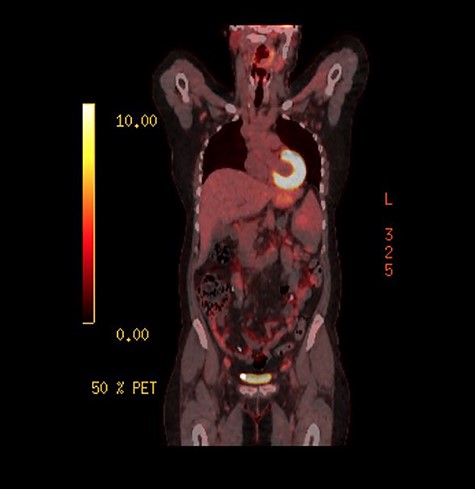

As the investigations thus far were non-conclusive, positron emission tomography (PET) scan was performed while awaiting for the result of the peritoneal biopsies. This was performed to look for possible primary malignancy. The splenic lesion demonstrated low-grade activity, below that typically seen in high-grade haematological malignancy as seen on Fig. 4. Combined with calcifications throughout the peritoneal cavity, an inflammatory or infective cause would be more likely.